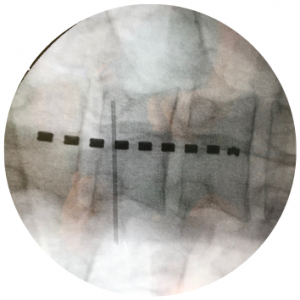

Hierbei wird unter Durchleuchtung (Röntgenstrahlen) eine Nadel neben dem Spinalnerv oder in das Nervenaustrittsloch des Nerven an der Wirbelsäule platziert. Anschliessend wird eine Mischung aus Kortison und einem örtlichen Betäubungsmittel gespritzt.

Es werden hauptsächlich die Nerven der Lendenwirbelsäule und Halswirbelsäule infiltriert.

Hierbei wird unter Durchleuchtung (Röntgenstrahlen) eine Nadel im Spinalkanal platziert. Entweder am Ende des Spinalkanals (Hiatus sacralis) oder von Dorsal zwischen den Dornfortsätzen. Dann wird eine Mischung aus einem Kortison und einem örtlichen Betäubungsmittel gespritzt.

Hierbei wird unter Durchleuchtung (Röntgenstrahlen) eine Nadel im Bereich der Gelenkkapsel oder des zuführenden Nerven zur Gelenkkapsel platziert. Dann wird eine Mischung aus Kortison und einem örtlichen Betäubungsmittel gespritzt.

Hier werden hauptsächlich das ISG (IlioSakralGelenk), die Facettengelenke der LWS und HWS infiltriert.